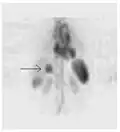

- 3D: ОФЭКТ — это трехмерный томографический метод, который использует данные гамма-камеры из многих проекций и может быть реконструирован в разных плоскостях. ПЭТ использует обнаружение совпадений для отображения функциональных процессов.

ОФЭКТ-сканирование печени ядерной медицины с мечеными технецием-99m аутологичными эритроцитами. Очаг высокого поглощения (стрелка) в печени соответствует гемангиоме.